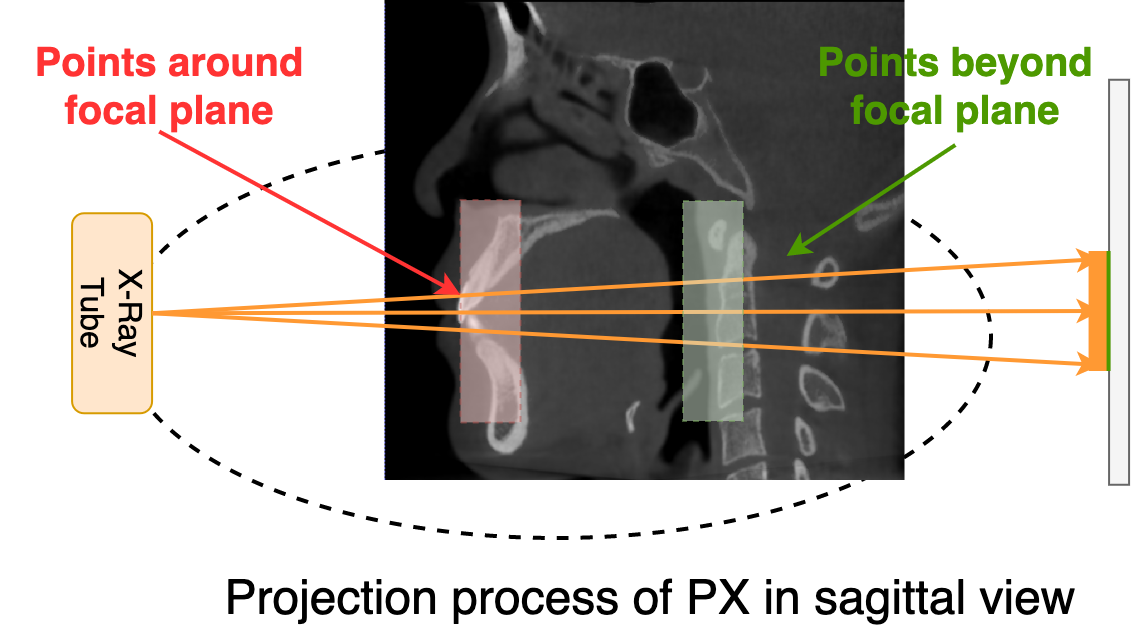

Refer to caption

Figure 4: We show the imaging process of PX in sagittal view in this picture. Unlike cameras, the X-ray tube used in radiology has a fixed trajectory and direction when moving, thus leading to limited variance in direction of radiation rays.

Different from NeRF-based models, where the camera has more freedom in position and angle, the X-ray tube in radiological scans generally moves in a fixed trajectory, leading to a limited direction and origin of radiation rays during the imaging. For example, as shown in the sagittal view of PX imaging in Fig. 4, radiation rays that pass through the oral cavity are approximately parallel to the axial plane. Taking advantage of this feature, we propose a different radiance field model that predicts a bunch of voxel values in the 3D space from a 2D coordinate. Given that the 3D object in radiology should be view-independent, our implicit representation model VNeXFsubscript𝑉𝑁𝑒𝑋𝐹V_{NeXF} can be defined as: